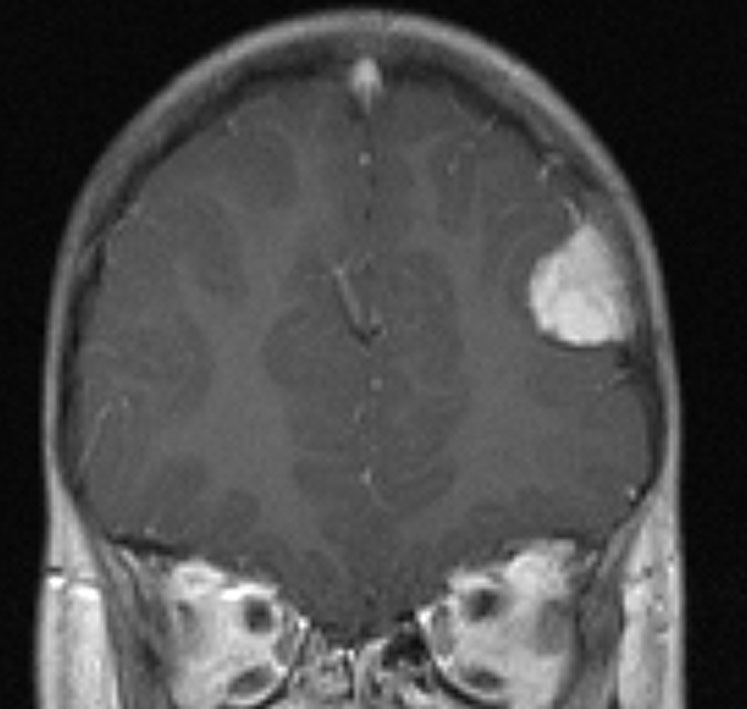

全脳照射後の脳内石灰化(青年期例)

1985年,17才のときに松果体ジャーミノーマで全脳照射45グレイ,18分割,1回2.5グレイの放射線治療を受けました。照射後の数年は普通に社会復帰ができていたということで,大学を卒業し,就職もしていました。しかし,20代後半くらいから認知機能低下(高次脳機能障害)が目立つようになりました。41才で脳幹部梗塞になりましたが,放射線治療が原因の脳血管障害でした。大脳にも小脳にも広範囲に脳内石灰化が散らばっています(白い点状に見えるもの全て)。30代からさらに進行悪化しました。脳の萎縮は目立ちませんが,MRIでは,大脳基底核の多数のラクナ梗塞,多数の海綿状血管腫,中大脳動脈の壁不整と狭窄もみられました。45才で介護施設に入所しています。このような所見は,1日線量2.5グレイを用いていた頃の小児患者さんでみられます。